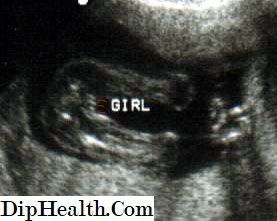

Изображение Анна, красным показала, где надпись girl